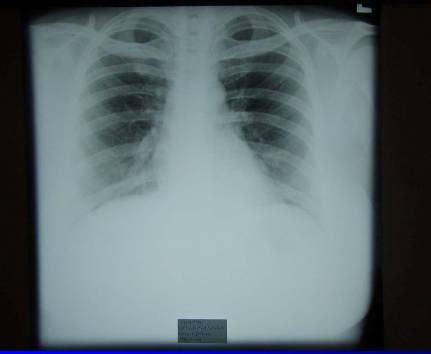

1.Generalizace (pac.L.U. . ––RTG, CT)

Generalizace (pac.L.U. . ––RTG, CT)